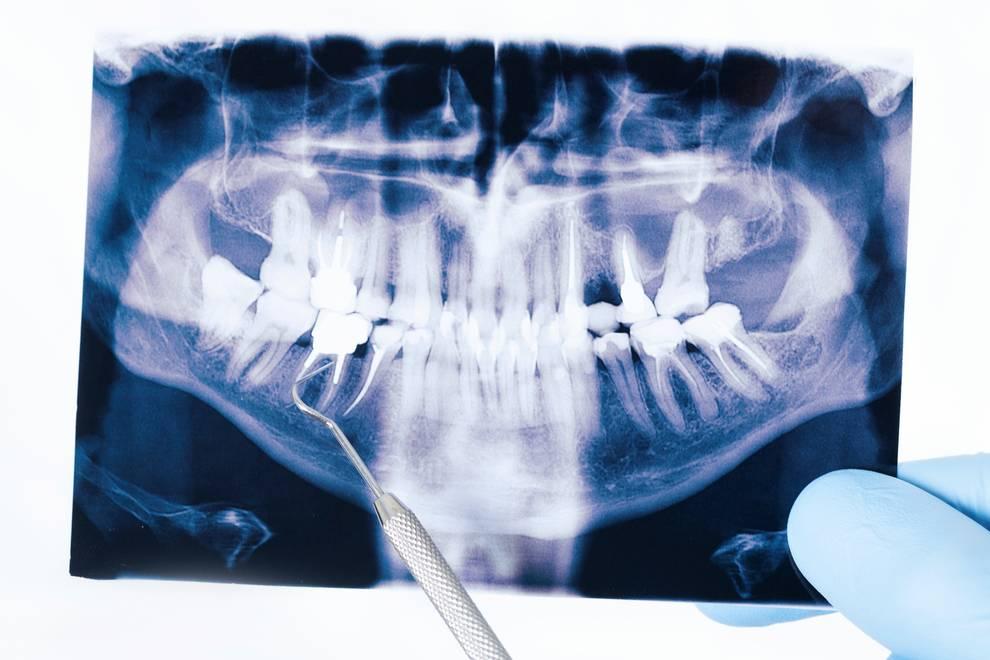

El prognatismo se corrige mediante la cirugía ortognática, un tipo de cirugía maxilofacial, combinada normalmente con ortodoncia. En esta intervención, el cirujano fractura la mandíbula (osteotomía mandibular) del paciente y la coloca hacia atrás, mediante placas y unos tornillos que se integran en el hueso.

prognatismo mandibular

Este procedimiento se realiza con anestesia general, y requiere una sola noche en el hospital. La cicatriz es invisible, ya que la cirugía se realiza mediante incisiones dentro de la boca.